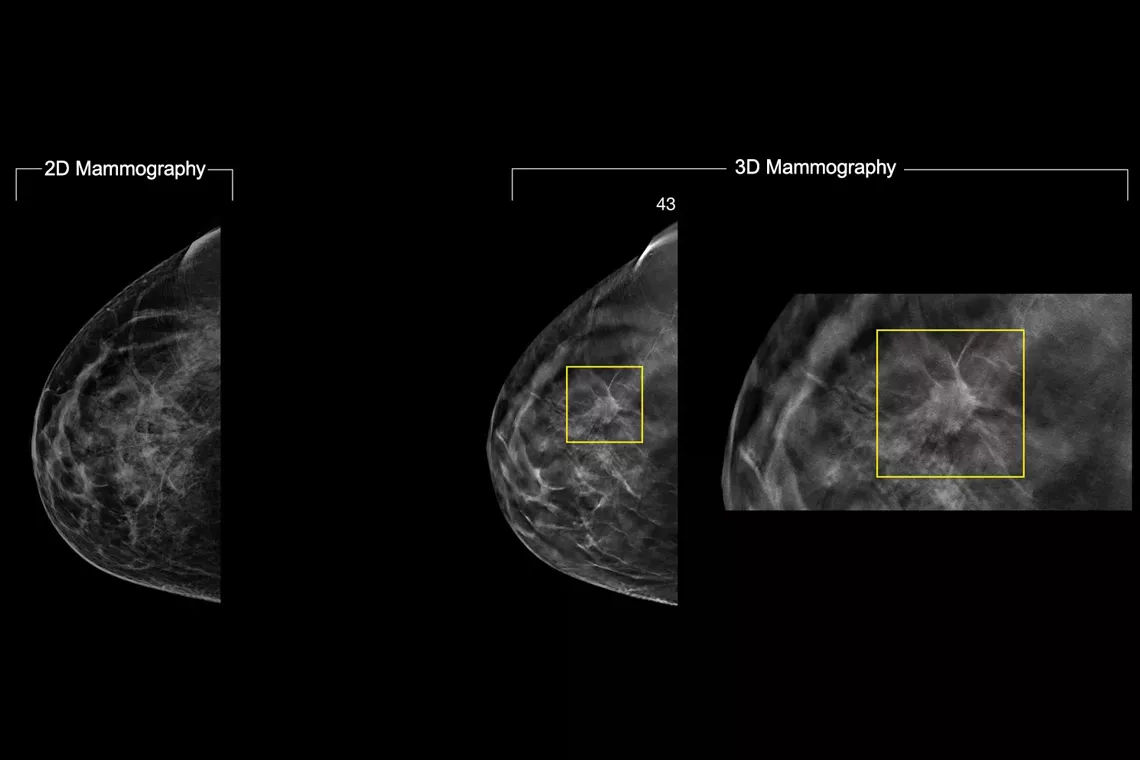

In a constantly changing clinical mammography environment, the flexibility and compatibility of ImageChecker 2D CAD Technology provides detection for conventional 2D images, as well as C-View™ and Intelligent 2D™ synthesised images derived from a tomosynthesis dataset.

- Easy navigation to the slice of interest in the tomosynthesis stack, when used in combination with Smart Mapping on synthesized 2D images

Image Gallery3